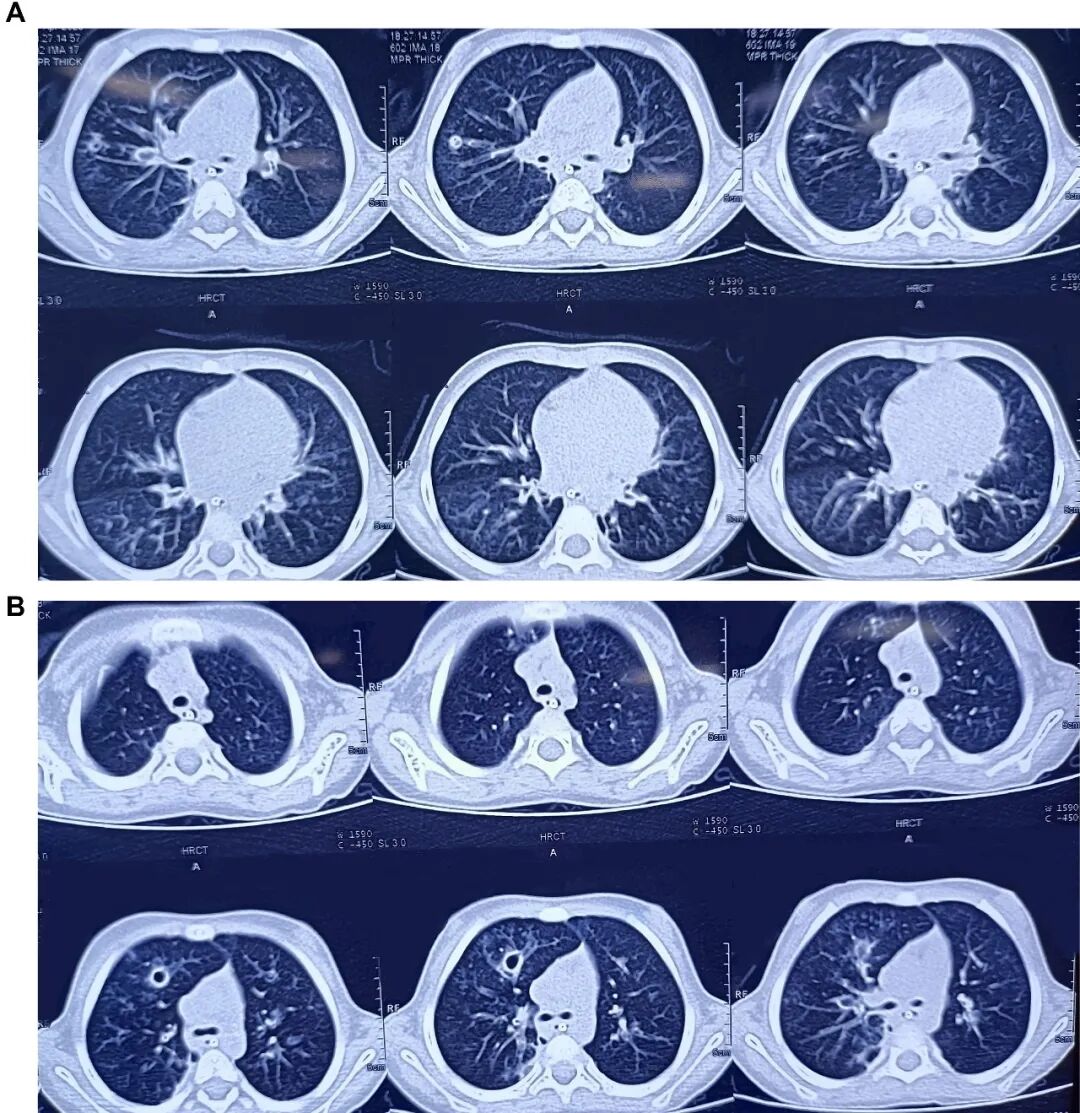

胸片显示双肺野过度充气,伴右肺中野不均匀浸润影及支气管壁增厚(图1)。胸部高分辨率CT扫描显示右肺上叶前段可见厚壁囊腔,可能存在交通,紧邻管壁明显增厚的亚段支气管——提示囊性支气管扩张(图2)。免疫功能缺陷检查已排除:HIV报告正常,免疫球蛋白谱正常,淋巴细胞亚群分析正常。IgA=54.67 mg/dL,IgG=990.32 mg/dL,IgM=404.186 mg/dL,IgE=16.3 IU/mL,CD3(T细胞)=2237.32 个/μL ,62.85% ;CD4 TH细胞=1165.21 个/μL ,32.73% ;CD8 T细胞=1065.26 个/μL,29.92%;CD4/CD8比值1.09均处于正常范围

2  A.胸部高分辨率CT扫描显示左右肺囊性支气管扩张,伴有空穴病变。B.胸部高分辨率CT扫描显示右肺上叶前段有厚壁囊性腔体,并有囊性支气管扩张的证据。